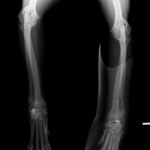

トイプードル 右遠位橈尺骨短斜骨折のALPSによる内固定